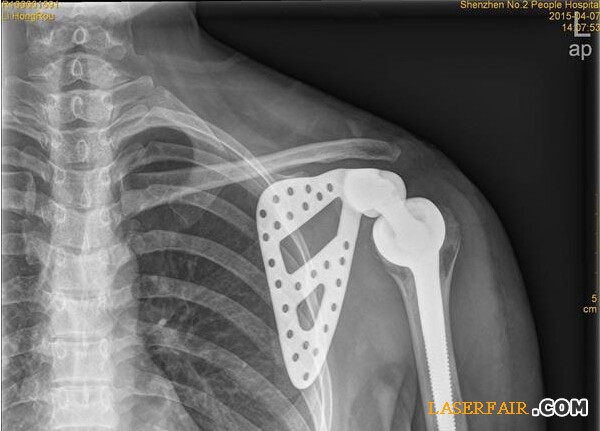

近日,深圳市第二人民醫院收治了一位27歲女患者,該患者肩胛部位的骨頭已經被腫瘤侵蝕四分之三,亟需手術切除。但是如果貿然切掉整個(ge) 肩關(guan) 節,不僅(jin) 手術風險大,恢複後病人生活也難以自理。於(yu) 是該院利用3D打印技術製備出與(yu) 患者肩胛骨完全匹配的鈦合金假體(ti) ,置換掉原來腫瘤壞死的肩胛骨,打造了一個(ge) 新的“肩膀”。

隨著3D技術的日臻成熟,該醫院與(yu) 3D打印公司展開治療研究,針對李女士的治療首次采用3D打印技術製備出與(yu) 患者肩胛骨完全一致的鈦合金假體(ti) ,並成功植入骨腫瘤患者體(ti) 內(nei) 。

“首先是3D打印人工製作肩胛骨模型,把采集到的李女士左邊肩胛骨大小、形狀等數據通過3D技術打印出完全吻合的模型。”深圳市第二人民醫院骨關(guan) 節、骨腫瘤科副主任醫師譚紀鋒介紹,然後根據模型設計出手術方案,在模型上標注手術的螺釘孔、切除邊界,實現手術精準化。”由於(yu) 3D模型采用的樹脂材料不能直接植入人體(ti) 內(nei) ,因此醫院將模型送至人工關(guan) 節製作廠,製作出鈦合金人工肩胛骨。在為(wei) 李女士進行腫瘤完整切除後,再將鈦合金人工肩胛骨植入患者體(ti) 內(nei) 。由於(yu) 3D打印實現了“量體(ti) 裁衣”,因而鈦合金人工肩胛骨能實現精準匹配。

14日,記者從(cong) 醫院獲悉,李女士的手術很成功,很快就可以出院了。據了解,這是深圳乃至華南地區首例肩胛骨3D打印鈦合金假體(ti) 植入術。